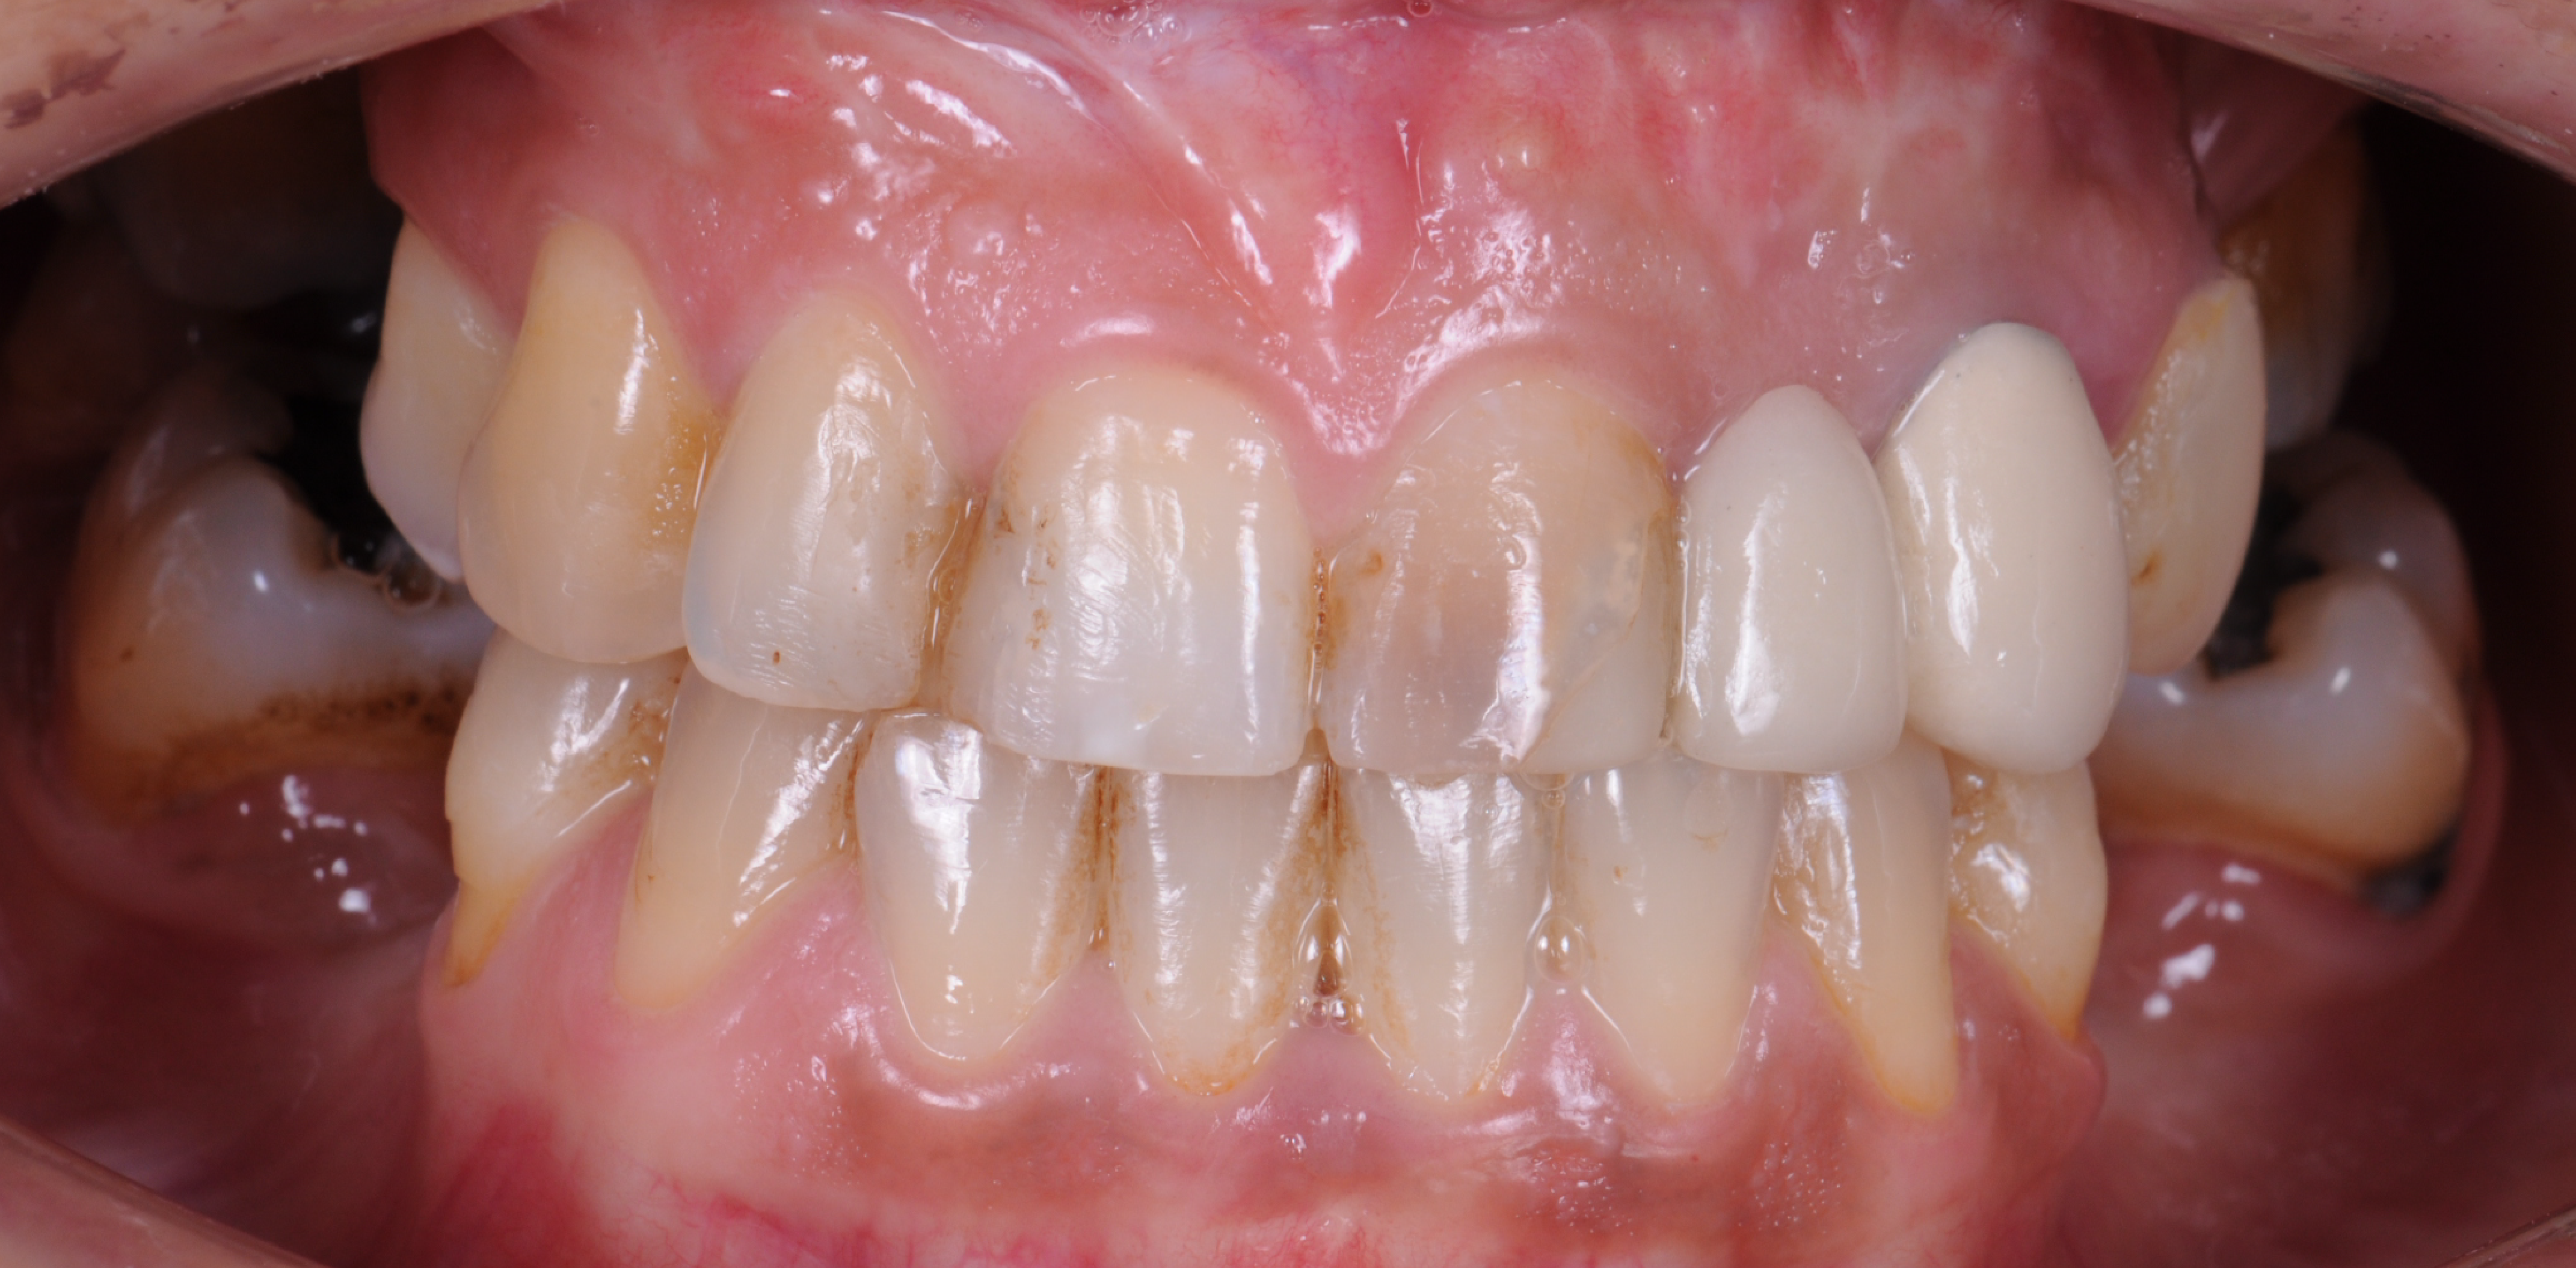

Sorriso inicial da paciente.